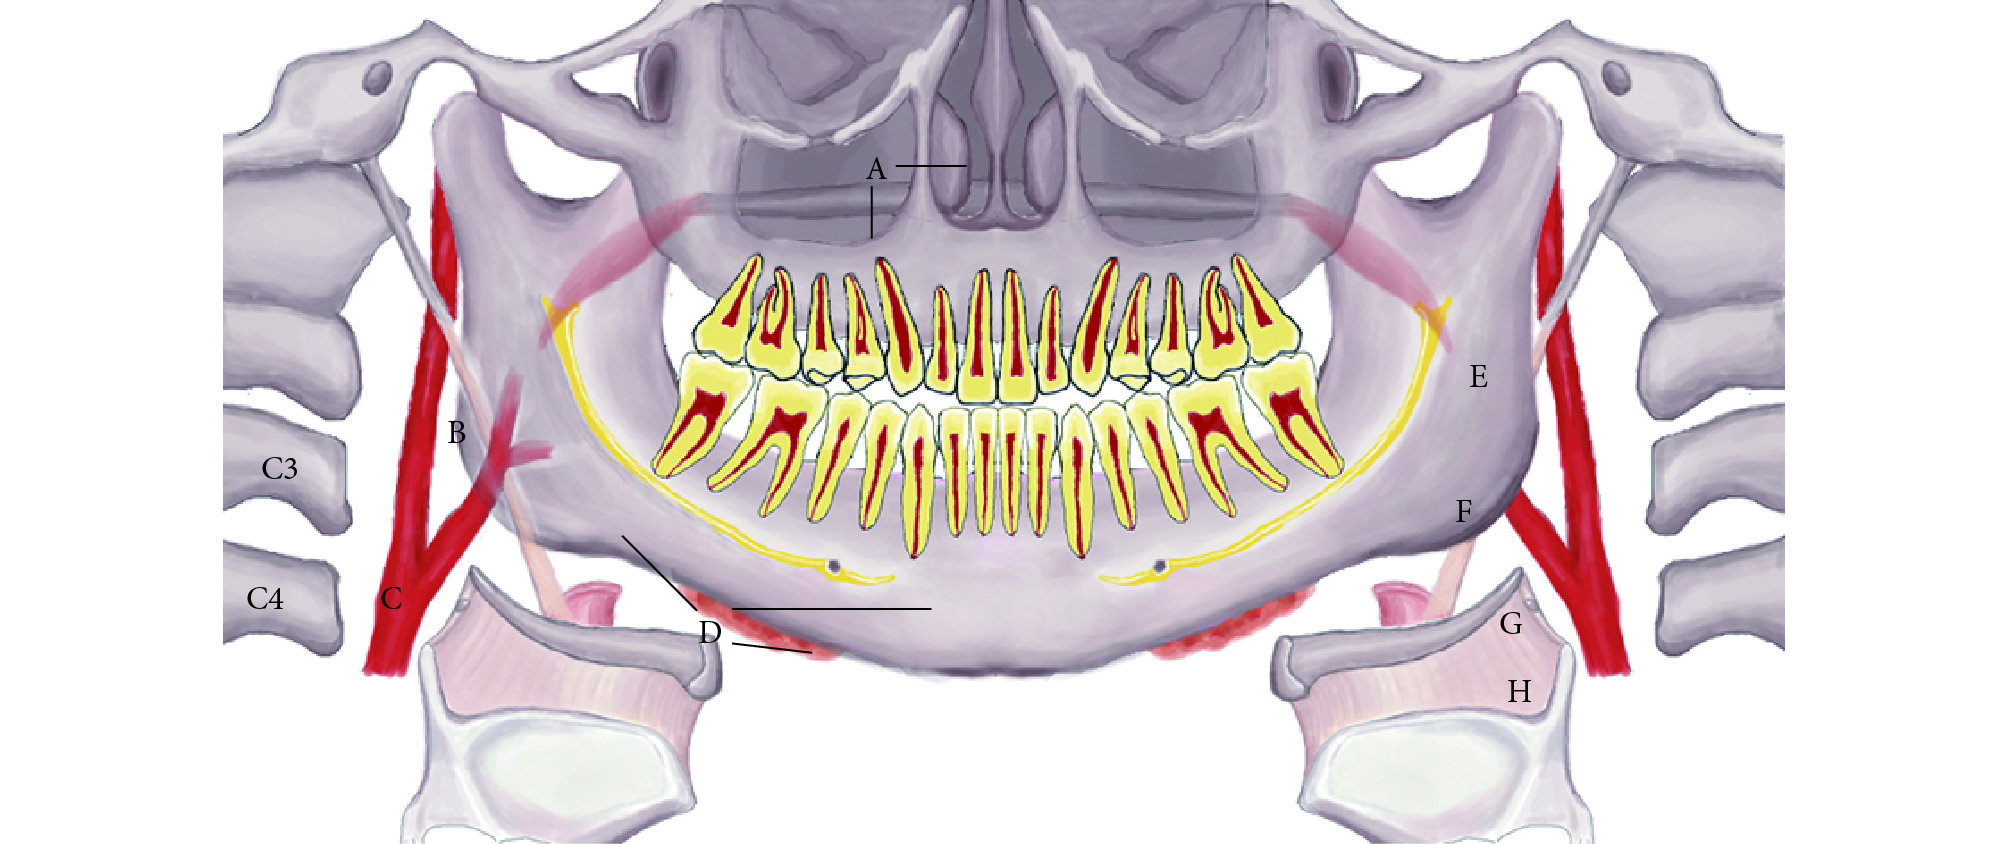

綜上,各類常見軟組織異常高密度影全景片分布如圖 7 所示,全景片上各類軟組織異常高密度影的特征總結見表 1。

A:鼻石與竇石;B:莖突舌骨鏈鈣化;C:動脈硬化;D:唾液腺結石;E:扁桃體結石;F:鈣化淋巴結;G:麥粒軟骨骨化;H:甲狀軟骨骨化